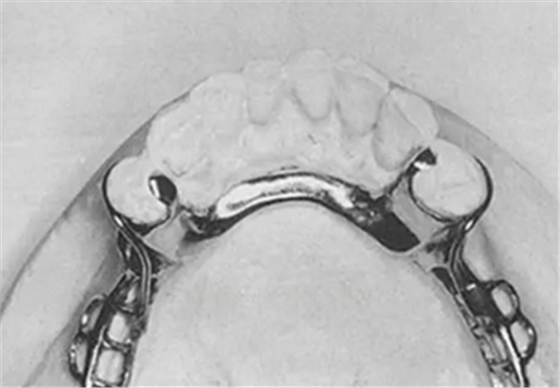

(二)RPA

(圖7,4頰側(cè)的固位臂也是畫蛇添足之作)

作為RPI的衍生物,RPA的設(shè)計也要滿足“讓游離端鞍基能無障礙下沉”這一理念。因此,RPA的R、P部分與RPI的設(shè)計要求完全相同,只是頰側(cè)固位臂為圓形卡環(huán)(Aker卡環(huán)),因此A的設(shè)計也就是RPA的關(guān)鍵所在,要求:①僅A卡臂堅硬部分的上緣與觀測線接觸,切不可高出觀測線(at,not above);②僅尖端進(jìn)入倒凹區(qū)。

(圖8,引自RPA的發(fā)明者Charles M. Eliason, D.D.S., M.A.)

RPA卡環(huán)對基牙的要求:①R、P部分與RPI相同;②A:頰面觀測線約在中1/3的位置,使近、遠(yuǎn)中均存在適量倒凹,且近中頰面倒凹至少0.25mm以放置卡臂尖。